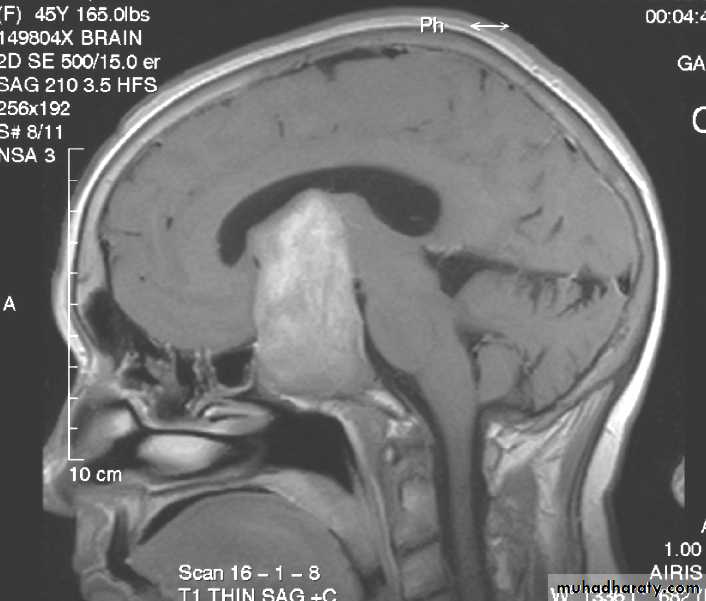

Astrocytoma Pre contrast MRI

Neurosurgery

Astrocytoma Post contrast MRI